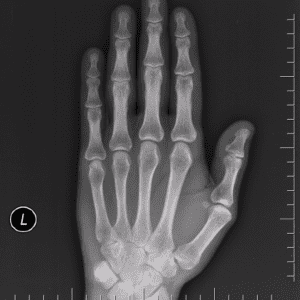

Gãy xương bàn tay

Lượt xem: 675» 29-10-2018 -